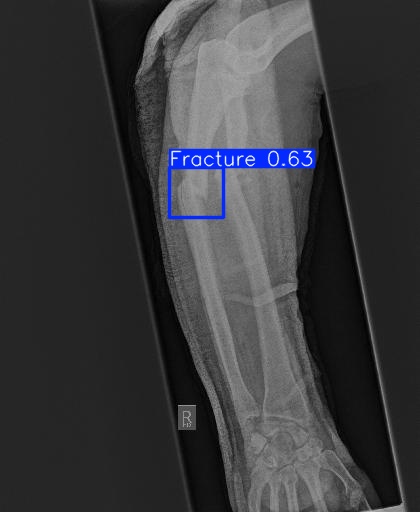

Bone 이미지 데이터 350장 중 Fracture 이미지 50장, Implant 이미지 50장, Bone 이미지 50장을 선별했다.

train과 val은 라벨링을 해야한다. 어제 라벨링을 했었지만, Fracture는 좀 넓게 잡고, Implant는 최대한 여러개로 쪼개는 느낌으로 라벨링을 다시했다.

| conf | 0.3 | 원래 0.9였는데 어제 결과가 너무 안 나와서 0.5로 바꿨다가 다시 0.3으로 바꿨다 |

그리고 predict 단계에서 IoU( Intersection over Union )를 낮추란다. 낮춰보자

IoU는 '교집합 영역 넓이 / 합집합 영역 넓이' 이다.